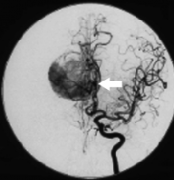

镰旁脑膜瘤通常由脑膜中动脉、胼胝体边缘动脉、胼胝体周围动脉的多个终末动脉分支和前镰动脉的分支提供丰富的供血,这可能使任何手术切除变得复杂。到达后进行的成像显示右侧...

大脑镰旁脑膜瘤 起源于大脑镰,约占全部颅内脑膜瘤的5-9%。库欣从外科手术的角度将大脑镰旁脑膜瘤与矢状窦旁脑膜瘤区分开来,报道大脑镰旁脑膜瘤常被覆盖的大脑皮层所掩盖,而...